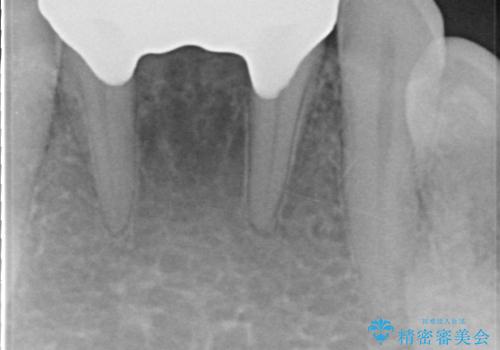

セラミックも強い衝撃で欠けないわけではないため、強度のあるフルジルコニアクラウンでブリッジを作成しました。

フルジルコニアクラウンはやや白すぎるといった難点がありますが、今回は強度を優先することにしました。

夜間の歯ぎしりによるチッピング、破折をふせぐため、ナイトガード使用をお勧めしています。